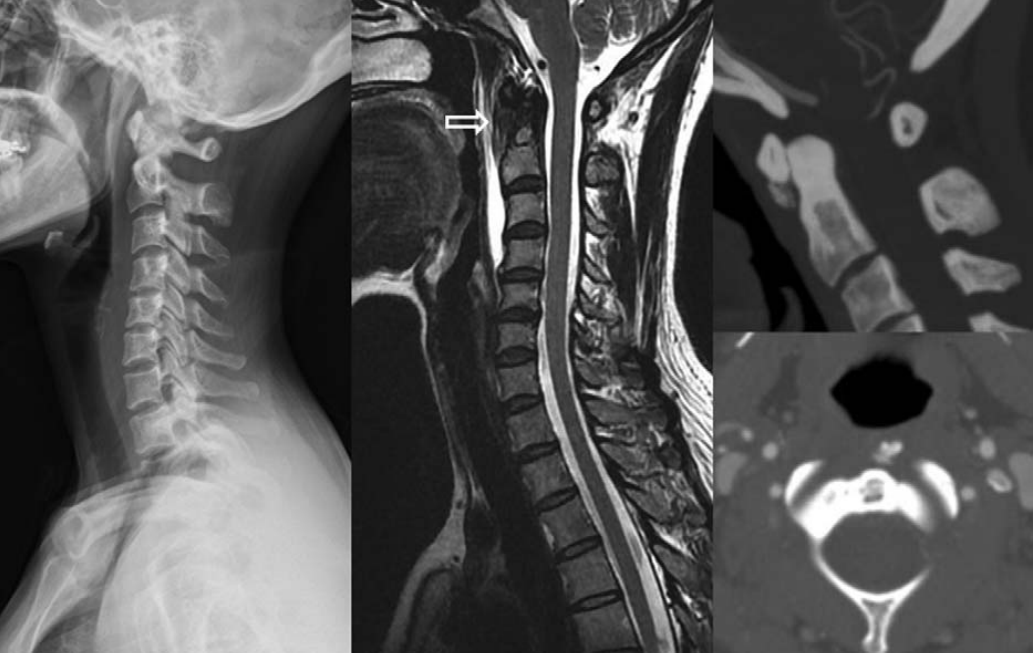

明确诊断主要通过影像学方法,颈椎CT是关键。颈长肌钙化性肌腱炎特异性的影像表现是C1-4椎体前缘软组织肿胀和积液与C1椎体前弓下方不规则钙化沉着共存。

图:C1椎体前弓下方不规则钙化沉着

图:椎前积液

图:椎前积液和C1椎体前弓下方不规则钙化沉着

图:椎前软组织肿胀

颈椎侧位片能够显示上颈椎前纵韧带和颈长肌组成的软组织影增宽,密度增高,正常时宽度为3-4mm,急性炎性水肿时可增宽到1cm以上,并可显示椎前软组织内的钙化影,一般位于C1-2水平。此外,还可见颈肌痉挛引起的颈椎前凸消失。颈椎侧位平片所见的发育性寰椎前弓的下方附属小骨片、寰椎前弓的撕脱骨折以及茎突舌骨肌韧带的钙化极易与本病所见的钙化混淆。

CT的高分辨率能够明确肌腱内的钙化,能够明确是钙化而不是其他骨骼来源的高密度影。钙化一般位于寰椎前弓的下方和枢椎齿状突的前方,少部分可位于下颈椎前侧。CT有助于明确椎体前积液的存在和排除其他病理表现,如骨折或脓肿。MRI对诊断不是必须,但有时可帮助确定软组织异常,排除咽后脓肿,脊椎炎或肿瘤。MRI检查T2加权在椎前可见局限性的裂隙样区域,大多位于C1-4水平,呈高信号改变,这反应是由于炎症引起的积液。T2加权、脂肪抑制序列和T1加权对鉴别积液和脂肪组织、含脂肪的骨髓以及咽后感染、脊椎炎有重要作用。MRI检查在钙化检查方面存在不足,T2加权呈低信号。

36岁女性,急性颈痛、吞咽困难伴颈部僵硬,MRI示C1-2前部颈长肌增厚呈低信号,提示钙化(长箭头)和C1-4椎前积液(无线箭头),经类固醇和止痛药治疗8天后症状消失,复查MRI提示上述表现消失。(PMID: 18765656)

C1-2前侧低信号(无线箭头)和C1-5椎前水肿(长箭头) (PMID: 19567634)

40岁男性,低热伴急性颈痛、张口困难1天,颈椎CT提示椎前钙化(箭头),经洛索洛芬60mg,每日三次,连续五天治疗,3天后症状改善,3月复查CT钙化消失。(PMID: 25918175)

32岁男性,颈肩部疼痛1月,喝水时轻度吞咽困难伴颈椎活动受限,无发热,化验指标正常,经非甾体抗炎药和秋水仙碱治疗后症状改善,4月后复查颈椎侧位片(D,E)钙化消失。(PMID: 25941110)